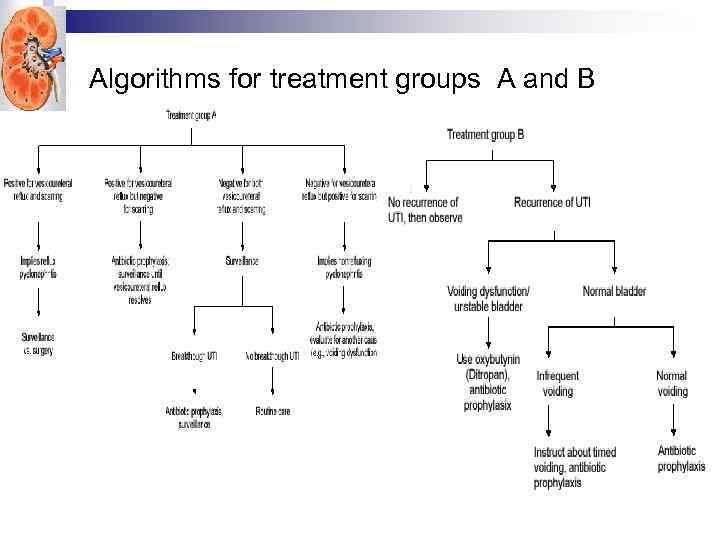

Algorithms for treatment groups A and B

Algorithms for treatment groups A and B